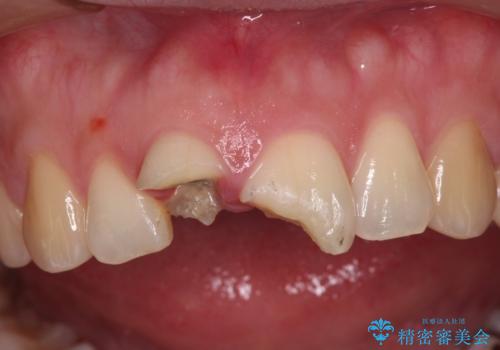

- 転倒により前歯を折ってしまったとのことで来院された患者様です。

右側の前歯は歯茎の中にまで及ぶ深い破折線があり、神経組織は既に失活していました。

左側の前歯は大きく歯冠が欠けてはいましたが、神経の生活反応が認められました。